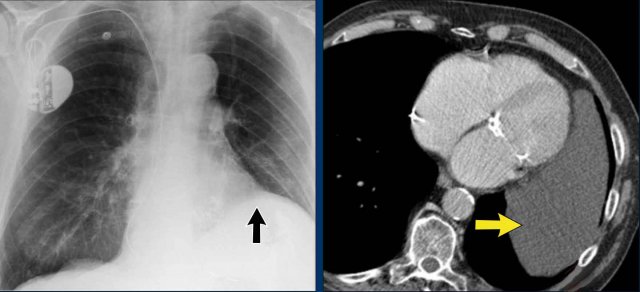

On chest radiography, a pericardial cyst may mimic an elevated left hemidiaphragm (black arrow).

However, CT more clearly demonstrates a fluid-filled cystic lesion contiguous with the pericardium (yellow arrow).